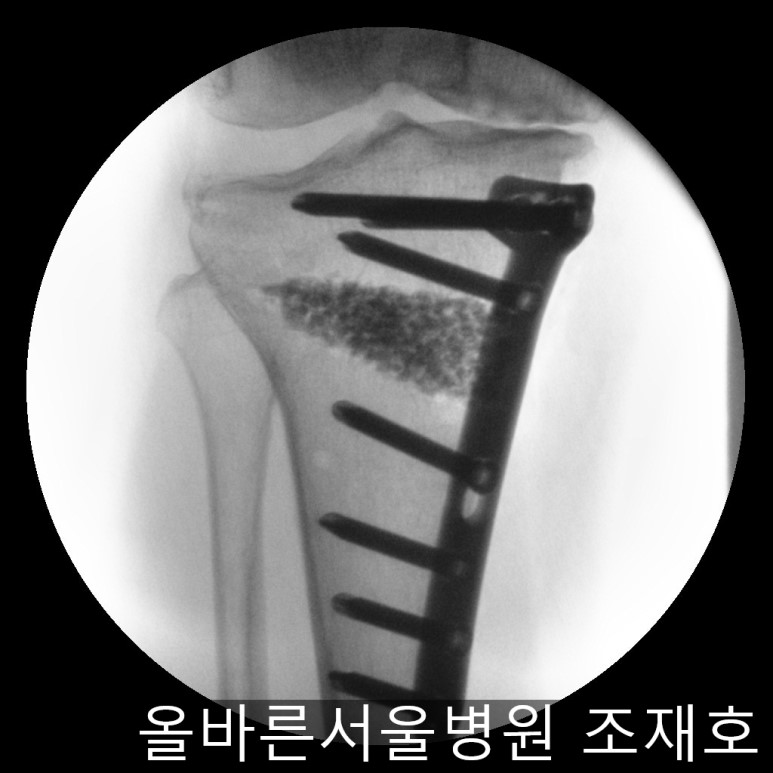

随后进行胫骨近端截骨术来矫正内翻变形。

需要进行20度矫正,因为没有这个度的矫正用模具,所以在手术前先计算内侧需要打开的程度。

如下图,适当的打开进行矫正。

之后用骨替代物填充,确认固定。

确保正面准确矫正。

侧位影响中也没有slop增加,矫正成功。

手术后可通过片子看到矫正后的正面样子。

此时内侧稍微分开,开始行走且软骨开始再生,内侧会更加分开。

侧面也矫正成功。